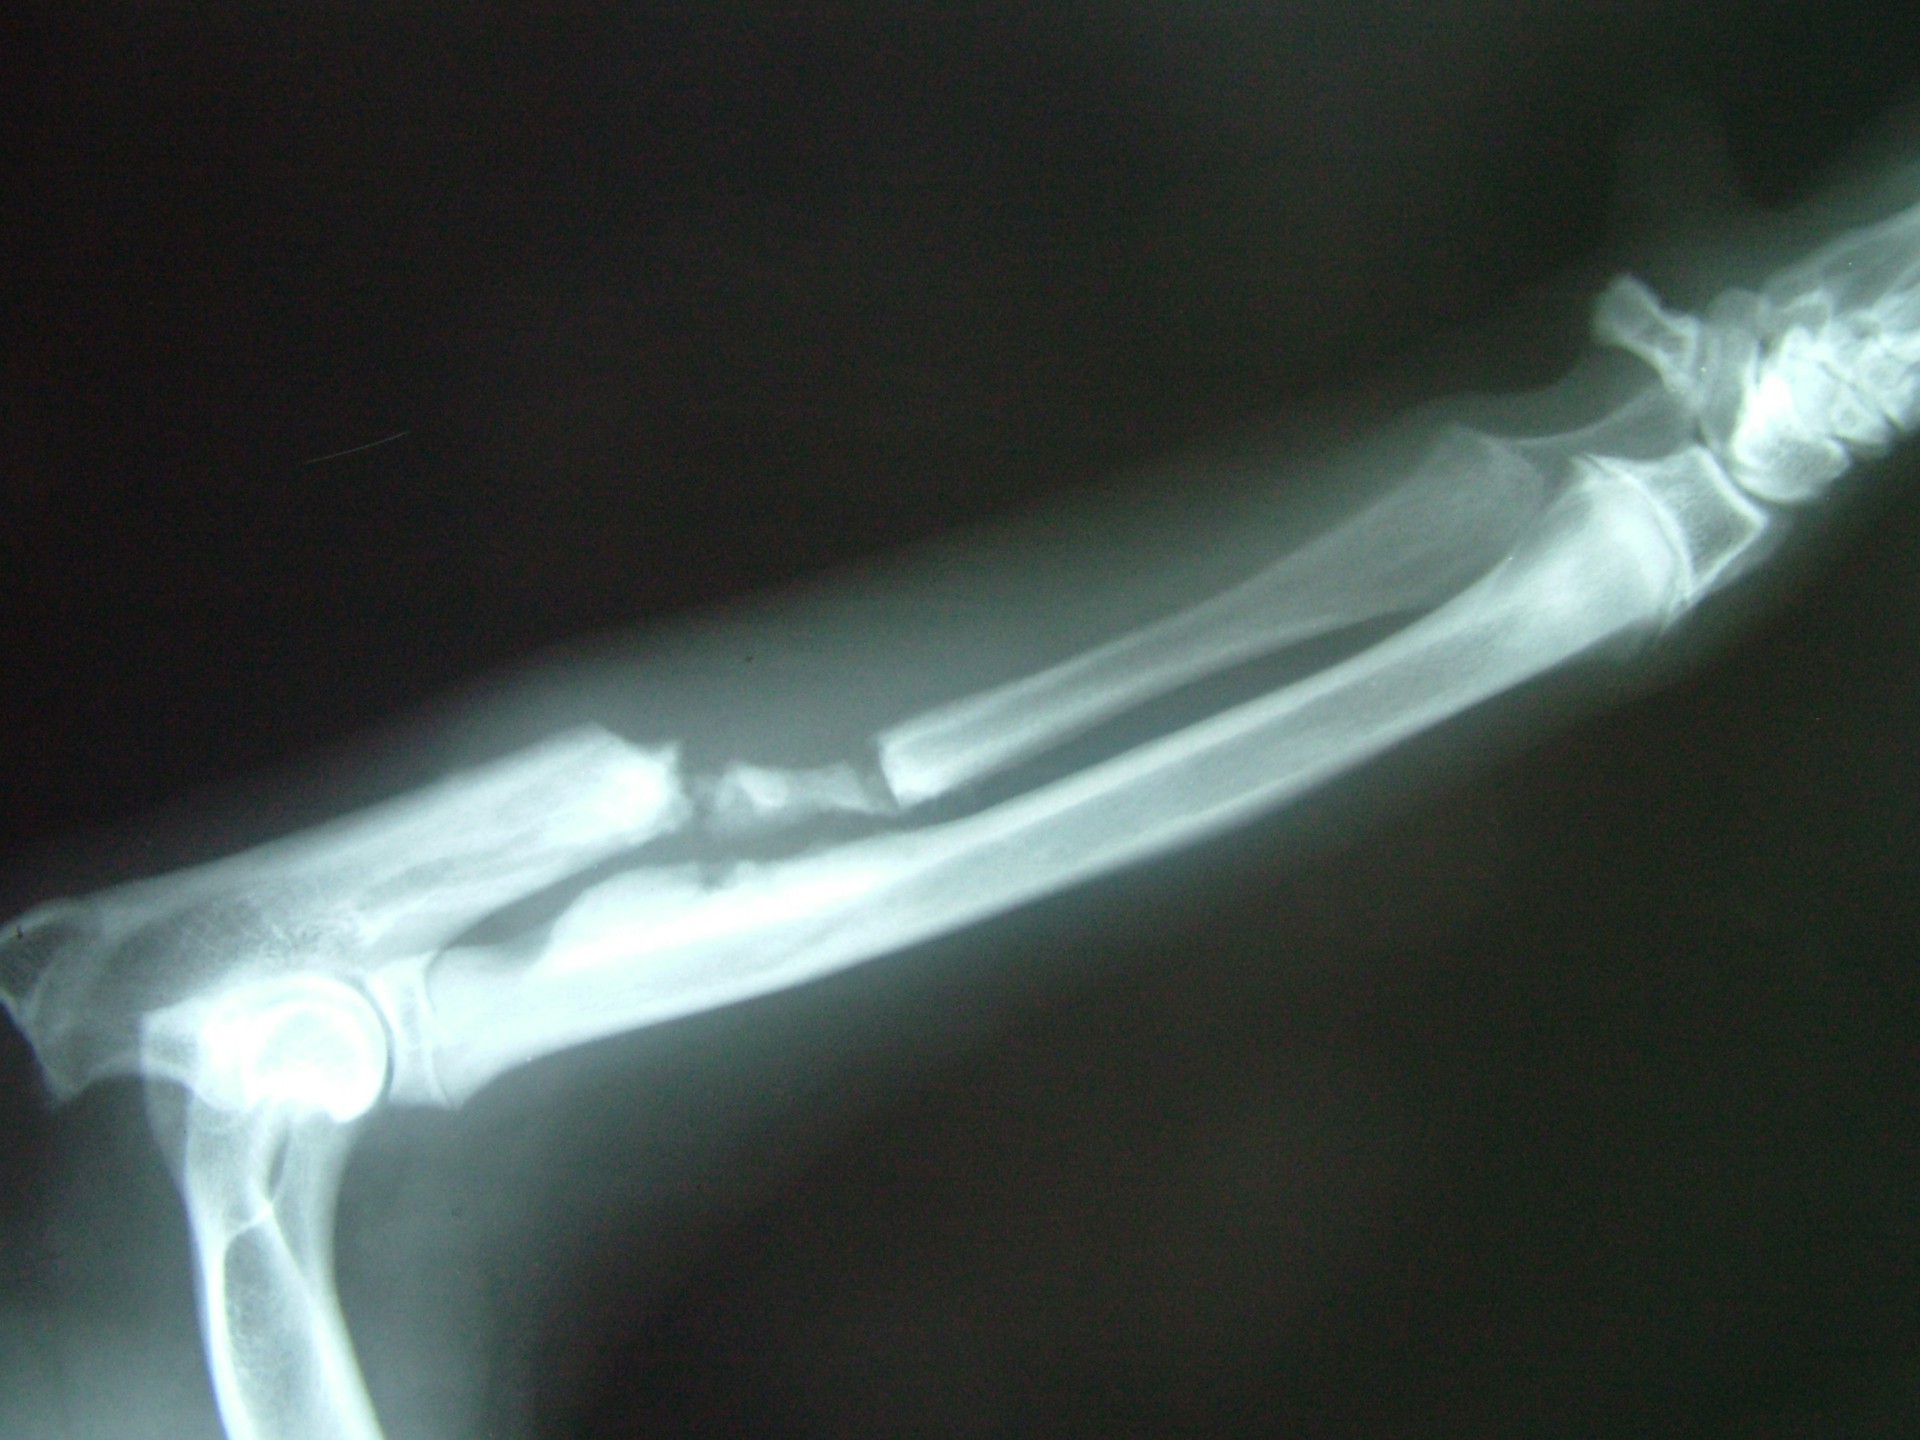

Az alkarcsont növekedési zónájának záródása (short radius)

Az alkarcsont növekedési zónájának záródása általában a könyökízületben un.: inkongruenciát okoz. A könyökízület működéséhez az azt alkotó 3 csont (karcsont, könyökcsont, alkarcsont) tökéletes illeszkedése elengedhetetlen. Azokban az esetekben amikor bármely 2, a könyökízület alkotásában résztvevő csont ízületi felszíne nem illeszkedik tökéletesen,rendellenes ízületi alakulásról, inkongruenciáról beszélünk. Ezekben az esetekben az ízületi felszínek nem megfelelő terhelődése azok kopásához, idült ízületgyulladáshoz, következményesen fájdalomhoz vezet.

Az alkarcsont alsó vagy felső növekedési zónájának lezáródása esetén a könyökízületben kialakuló inkongruencia az ízület mozgásának fájdalmasságához, a mozgáspálya beszűküléséhez vezet. Paradox módon az ilyen elváltozás esetén is (mivel az alkarcsont a teherviselő csont) a könyökcsont osteotomiájával, annak növekedésének korlátozásával gyógyítjuk a beteget.